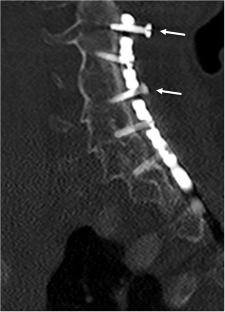

We identified 5 patients with the mean age of 4.4 years (range 2–6 years) who all had spinal cord injury with subluxation or dislocation at C6–7. All patients underwent posterior cervico-thoracic fixation with mandibular instrumentation from C2 to the upper thoracic spine. There was one complication of a right vertebral artery occlusion by screw placement, which did not cause harm. Suboptimal screw placement was detected in 18.4% of screws, but no revision was needed, since it was asymptomatic. All patients fused successfully without significant hardware failure. The mean time of follow up was 91 months ranging from 33–187 months.

Mandibular screw and plate fixation was effective to treat the acutely traumatic unstable subaxial cervical spine in the young pediatric population. The rate of suboptimal screw placement may be reduced by placing shorter screws into the lamina, pedicles, or facets if the plate hole does not align for a standard trajectory needed for lateral mass or pedicle screw placement.